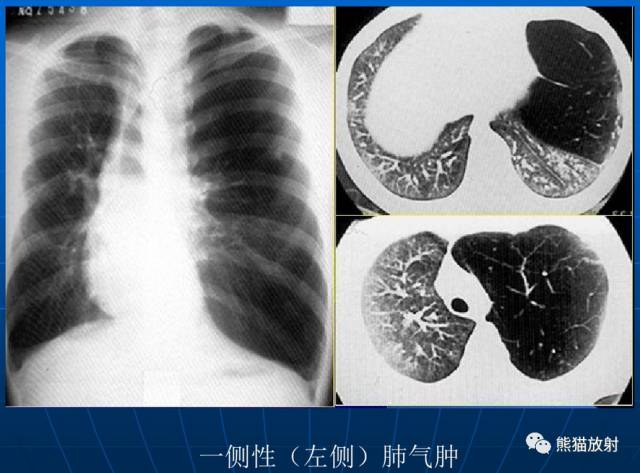

| 一侧性肺气肿 |

(1)过度透明肺可以是单侧或双侧的病变。若是单侧的,它可以侵及全肺、一叶、一段甚至一个小叶。

(4)真正的肺疾病导致单侧过度透明肺是肺血流量减少的反应。其原因包括心脏分流、肺栓塞、肺气肿、支气管内肿块和闭塞性细支气管炎。

(5)X线诊断肺气肿是一个有争论的课题。大多数人同意血管的变化与肺气肿的病理诊断紧密相关。对早期肺气肿的诊断CT较平片敏感。